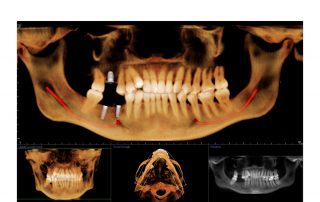

i-CAT FLX V10

The i-CAT FLX V10 combines highly precise cone beam 3D technology with flexible planning and treatment tools. The i-CAT offers a full suite of solutions to meet the needs of your practice. V10 scan sizes range from an adjustable 8cm x 5cm to 16cm x 10cm.